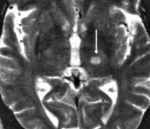

Термин « инфаркт мозга» приобретает все большее распространение с широким применением методов нейровизуализации, позволяющих уточнить локализацию и размеры ишемического очага и предположить его природу. Однако по своему смыслу термин «инфаркт мозга» не вполне эквивалентен термину «ишемический инсульт».

Ишемический инсульт – клиническое выражение инфаркта мозга, а инфаркт мозга – морфологический субстрат ишемического инсульта.

— КТ и/или МРТ-ангиография;